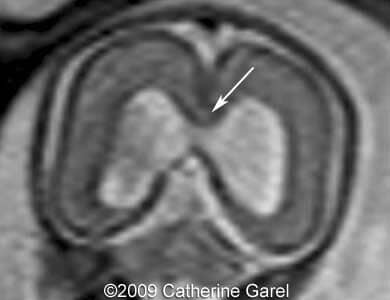

Images 9,10: Images 9, 10 show a fusion in the posterior frontal and parietal regions, indicated by arrows.

Case262_9a

Case262_10a